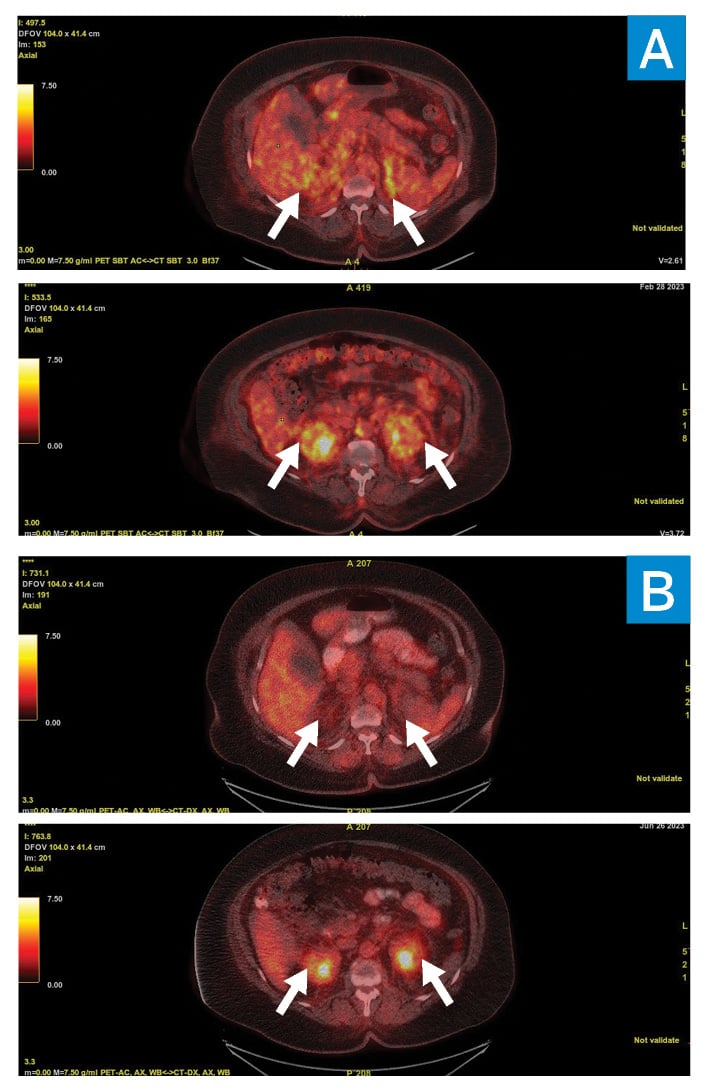

A CT-guided adrenal gland biopsy targeting the soft-tissue infiltration that was most avid on positron emission tomography (PET)–CT scanning (Fig. 3) demonstrated an inflammatory infiltrate composed predominantly of histiocytes (highlighted by CD163 immunoreactivity) mixed with lymphocytes, eosinophils, and plasma cells. This raised concern for histiocytosis, particularly Erdheim–Chester disease (ECD). MRI of the legs confirmed the presence of classic sclerotic lesions in the distal tibia and femoral diaphysis. The patient was referred to oncology for further management. A biopsy of the xanthelasma was recommended for mutation testing and was consistent with xanthomatous non-Langerhans histiocytic infiltrate with Touton giant cells in the dermis and extending into skeletal muscle. Mutational analysis of both tumor material and peripheral blood cell-free DNA demonstrated the BRAF V600E mutation. The diagnosis of ECD was confirmed by this constellation of findings, and the patient was started on cobimetinib, a MEK inhibitor. At 2-month follow-up, PET/CT scanning and cardiac MRI showed the pleural and pericardial effusion had completely resolved, with marked decrease in the soft-tissue infiltration.

Figure 3

A PET/CT scan showing 18F-fluorodeoxyglucose (FDG)– avidity pre- (A) and post- (B) treatment in the adrenals (top) and perinephric space (bottom).